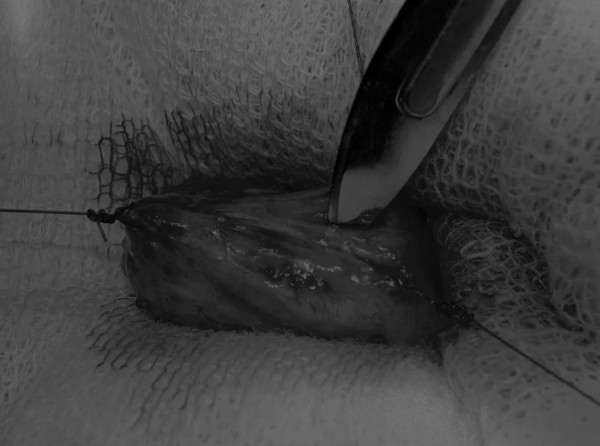

在中线开腹手术后,确定膀胱,将其取出并隔离(图1)。为了使膀胱持续暴露,可在膀胱中线两侧各放置一根固定缝线(图2)。

图1 将膀胱从腹腔中取出,用无菌外科敷料隔离。为了防止膀胱滑入腹部,可在膀胱顶部放置一根固定缝线,由助手通过止血钳夹住固定缝线做持续牵引